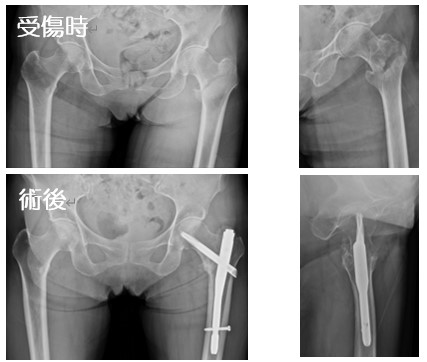

eb4acaabee778636e6a97f8010df93。大腿骨頸部骨折の手術【手外科・外傷】 | おおさかグローバル。Frontiers | Impact of Periosteal Branches and Septo。「大腿骨近位部骨折 : 大腿骨頚部・転子部・転子下骨折の手術手技」高平 尚伸 / 最上 敦彦 / 神田 章男 / 北田 真平定価: ¥ 14000#高平尚伸 #高平_尚伸 #最上敦彦 #最上_敦彦 #神田章男 #神田_章男 #北田真平 #北田_真平 #本 #自然/医療・薬学・健康 サージカルテクニック裁断済みです。裁断にご理解頂ける方のみご購入よろしくお願いします。Treatment of moderate and severe hallux valgus by performing。書き込みは見たところございません。ペリー 歩行分析 正常歩行と異常歩行。アシックス やり投げ ジャベリンプロ3。